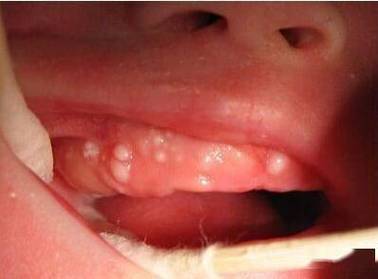

宝宝口腔内红色血点咋回事?

看到宝宝口腔内有红色血点,家长肯定会很担心,别慌,这其实是一个比较常见的现象,原因多种多样,有些是正常的生理现象,有些则需要引起注意。

- 手足口病:这是最常见的原因之一,在发病初期,宝宝的手、足、臀部可能出现皮疹,同时口腔黏膜(尤其是颊黏膜、舌、牙龈、上颚)会出现针尖大小的红色斑丘疹或水疱,水疱破溃后会形成灰白色的小溃疡或糜烂面,周围有红晕,这些破溃点有时会伴有少量渗血,看起来像血点。

- 其他病毒:如疱疹性口炎,也可能在口腔内出现成簇的小水疱,破溃后形成溃疡并可能出血。